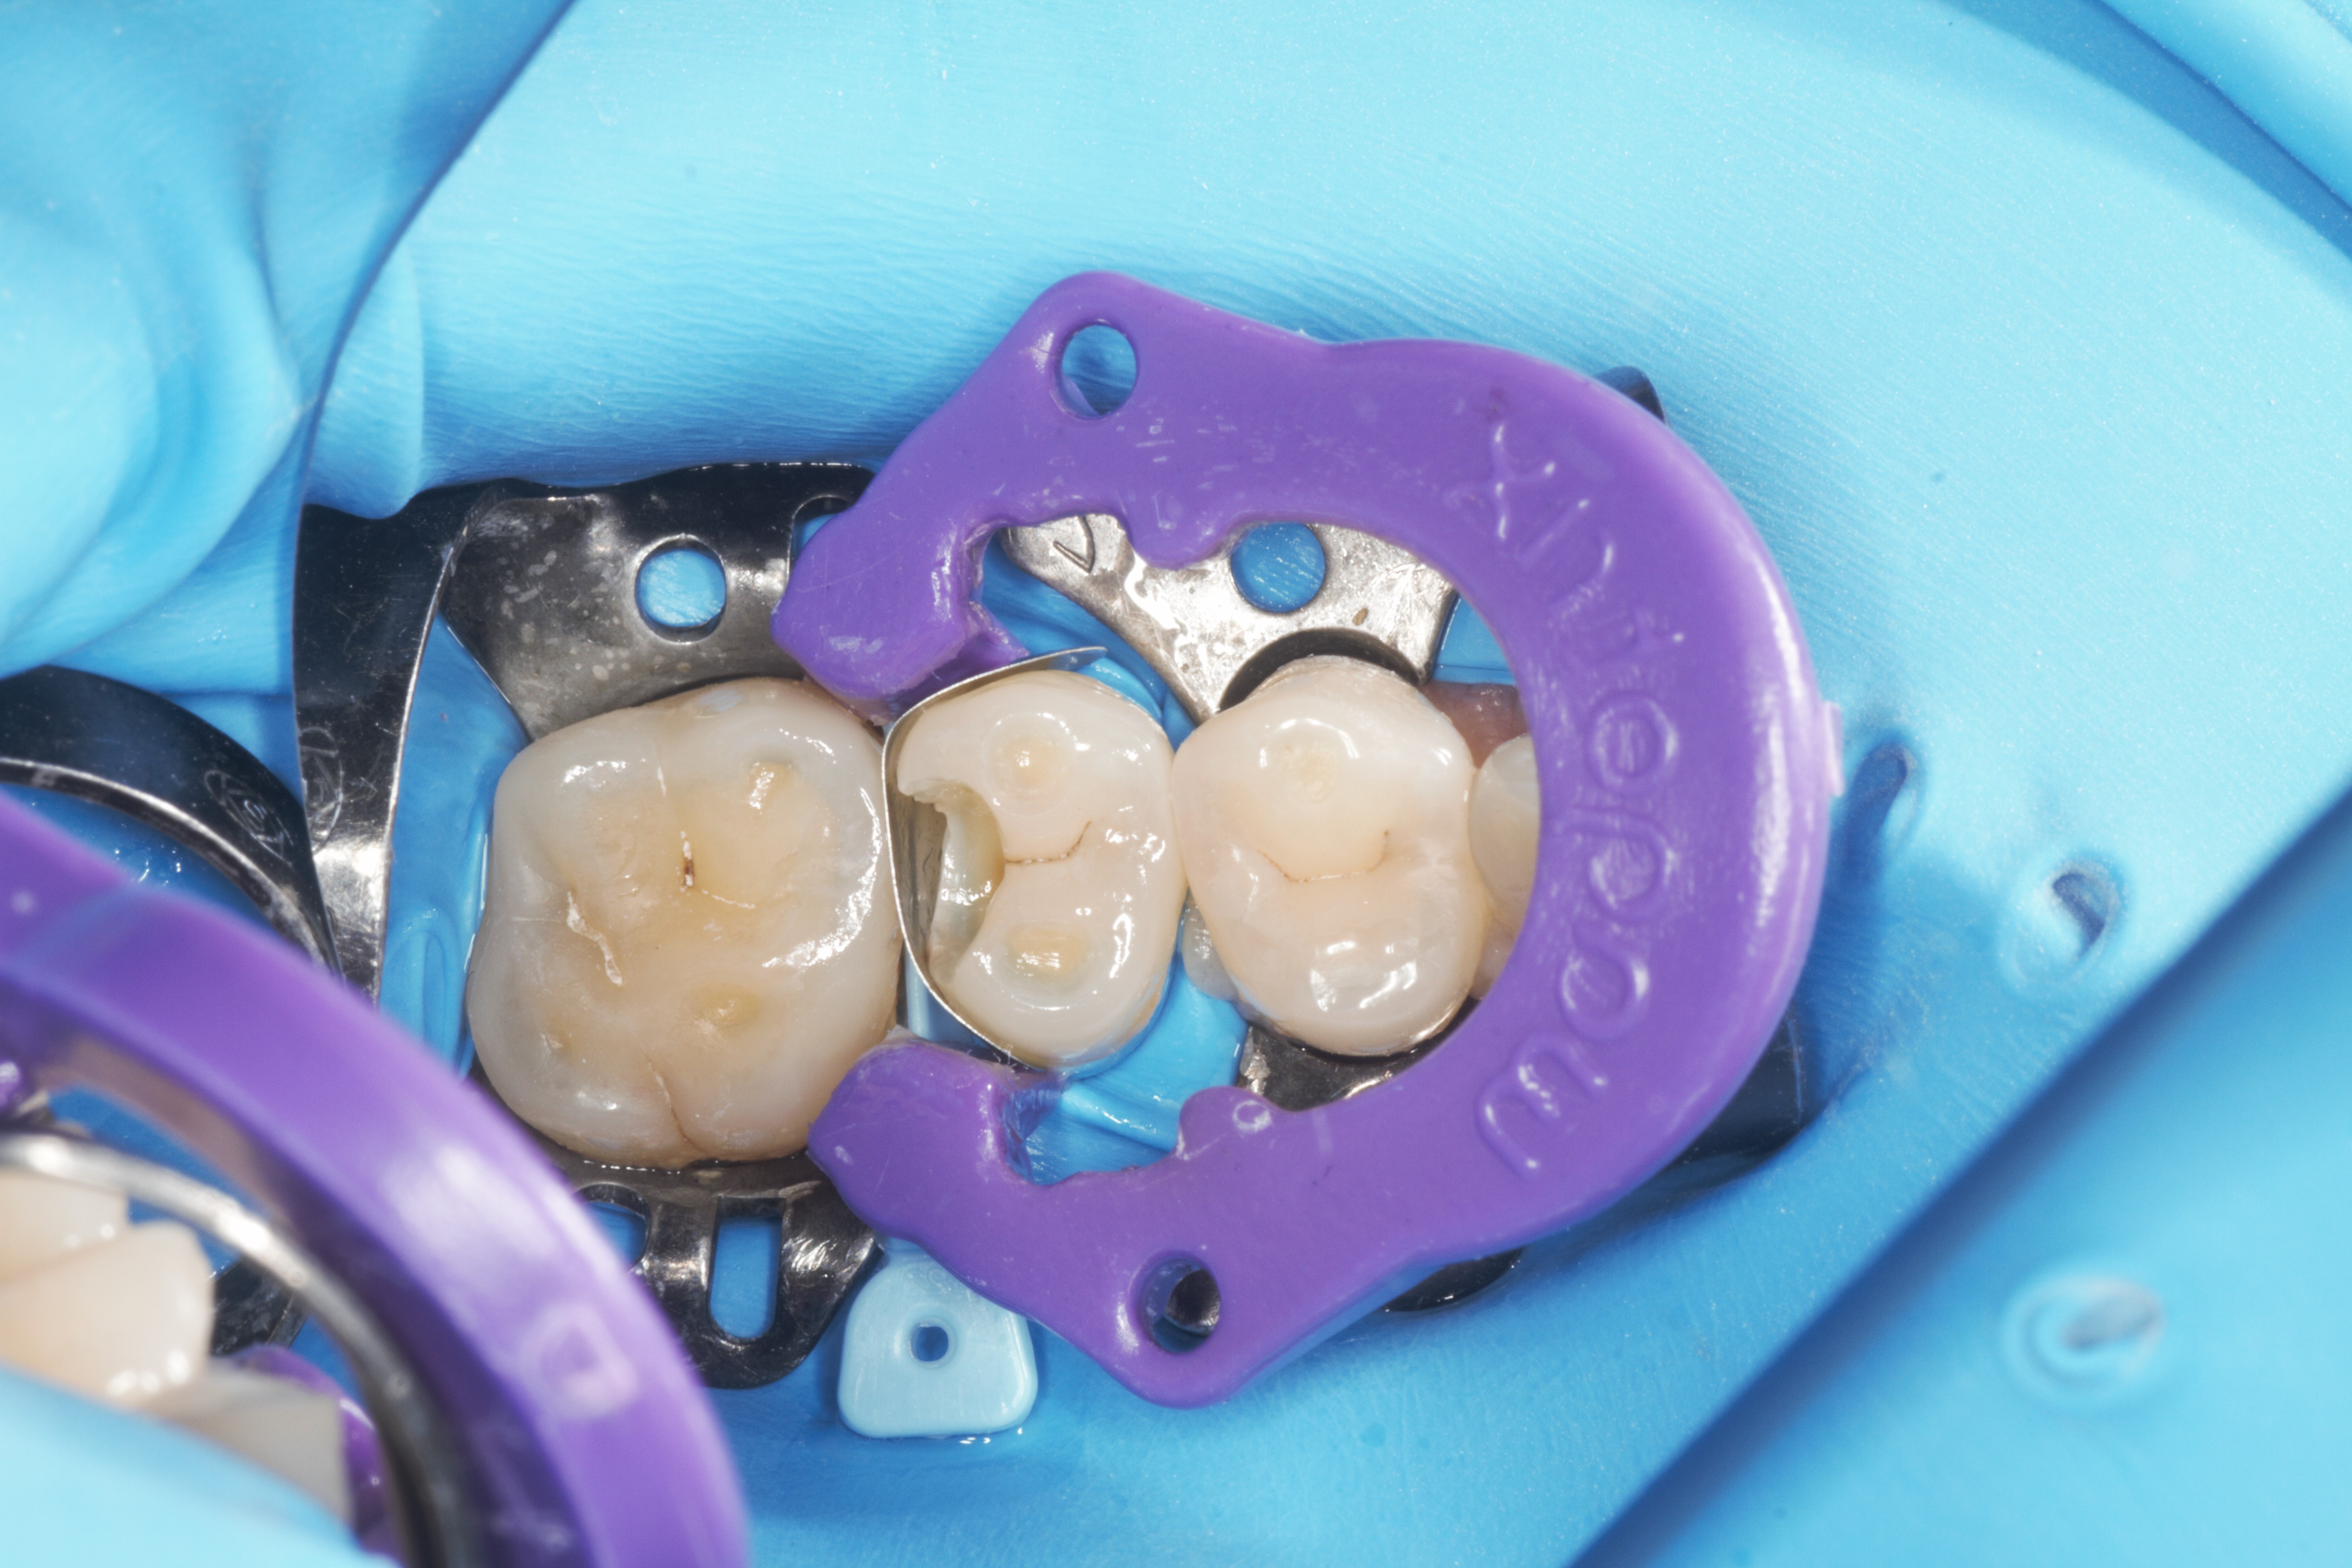

- Эстетическая реставрации жевательной и фронтальной группы зубов современными пломбировочными материалами, диагностика кариеса на ранних этапах развития, предупреждение образования вторичного кариеса в области запломбированных зубов

- Подготовка зубов к ортопедическому и ортодонтическому лечению, с учетом назначенного плана лечения